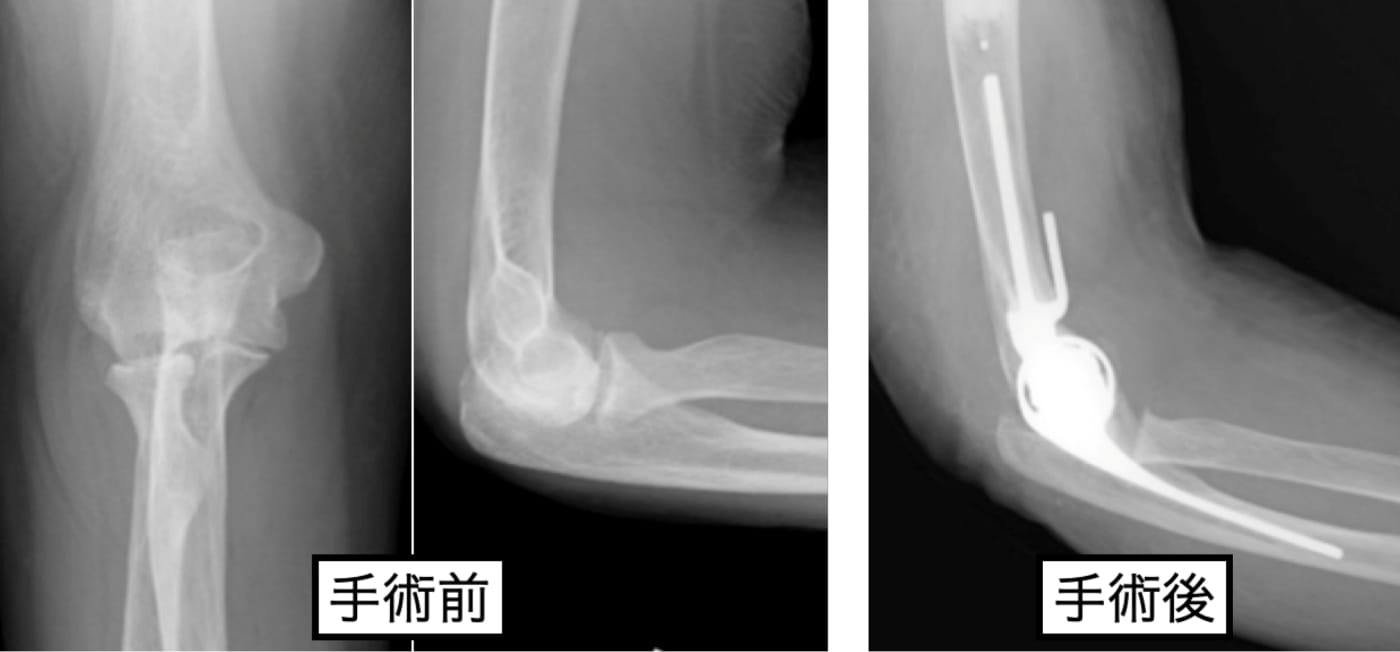

リウマチによる肘部変形

適応あれば、人工関節を用いた再建術を行っています。術後は上肢のリハビリテーションに特化したハンドセラピストによる後療法を行っています。